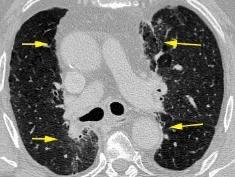

Triada de Garland

Ganglios paratraqueales derechos e hiliares bilaterales

95% de pacientes tienen ganglios hiliares bilaterales aislados o con afectación mediastínica (espec. paratraqueal derecho).

Criado E et al. Pulmonary sarcoidosis: typical and atypical manifestations at high-resolution CT with pathologic correlation. Radiographics. 2010